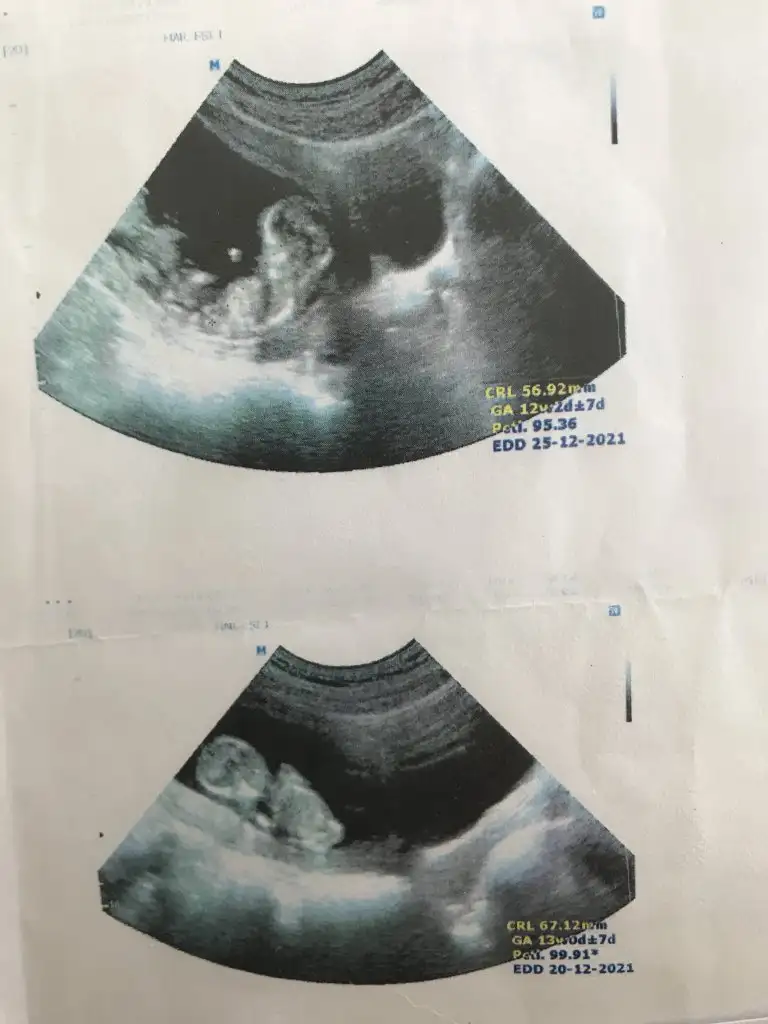

.Tahmin eder misiniz? İlk resim 6. Hafta vajinal ultrason 2. Resim 12+3

Benim ikiz bebeklerime de bir tahminde bulunurmusunuz

Eki Görüntüle 2889233

Eki Görüntüle 2889229 Eki Görüntüle 2889231

Haftası büyük olan erkek

haftasi küçük olan kız![]()